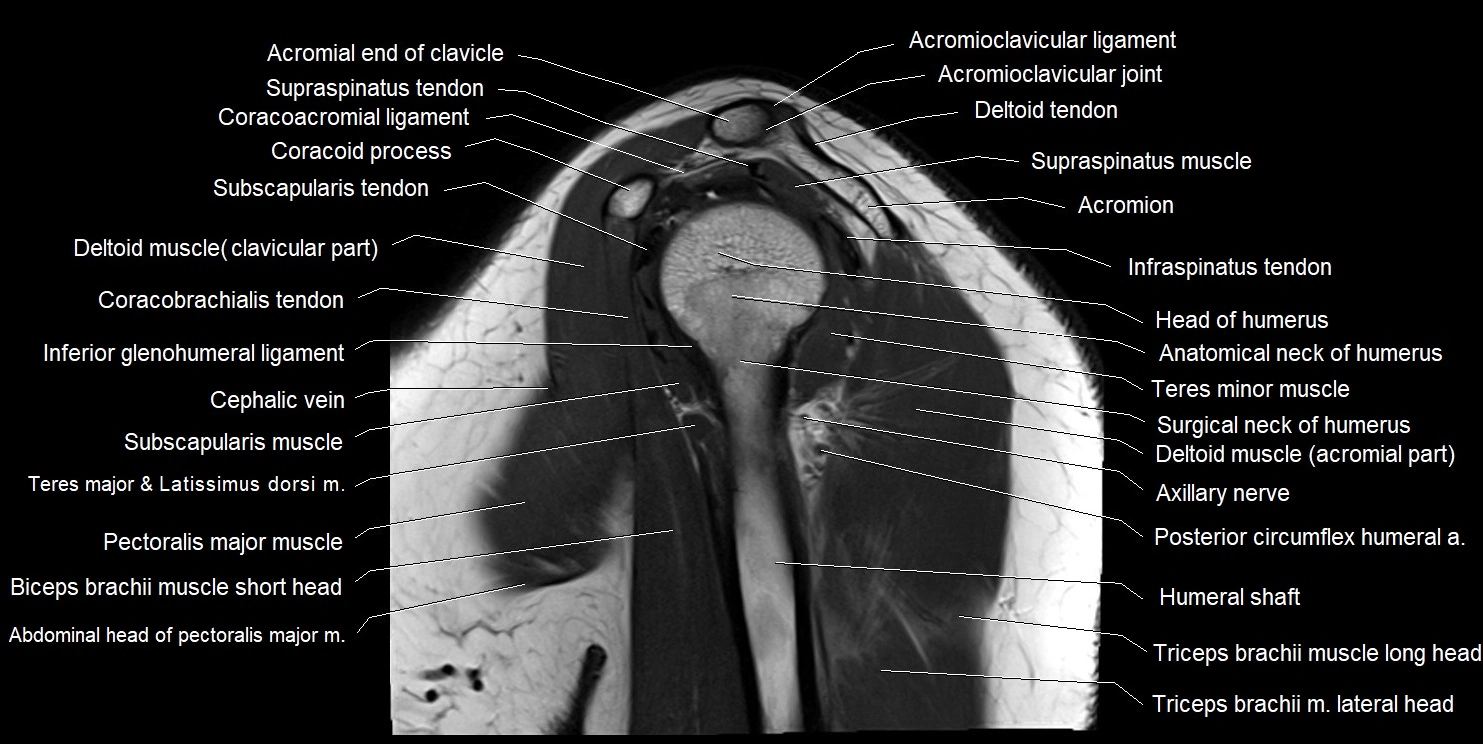

MRI images

image